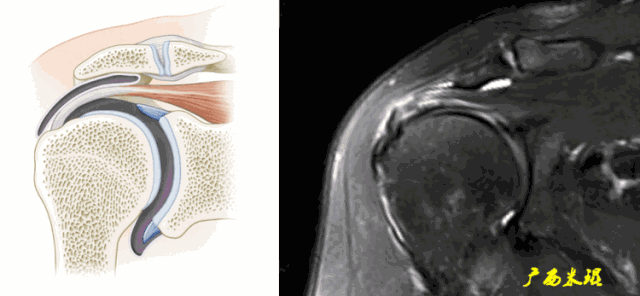

(2)肩峰下滑囊炎

肩峰下滑囊是一个非常重要的解剖结构,大部分肩关节的病变都会波及,肩袖损伤更不例外,同时,肩峰下滑囊炎的病变也可以波及到肩袖等组织。肩峰下滑囊炎在MRI上表现是非常明显的,如果其正常,肩袖一般也正常。

a.肩峰下滑囊增大,是肩袖损伤必有的表现。

b.肩峰下滑囊贯通(与关节腔相通),预示着肩袖的完全撕裂。

c.钩状肩峰,发生肩袖撕裂的机会大,但绝不是百分之百。